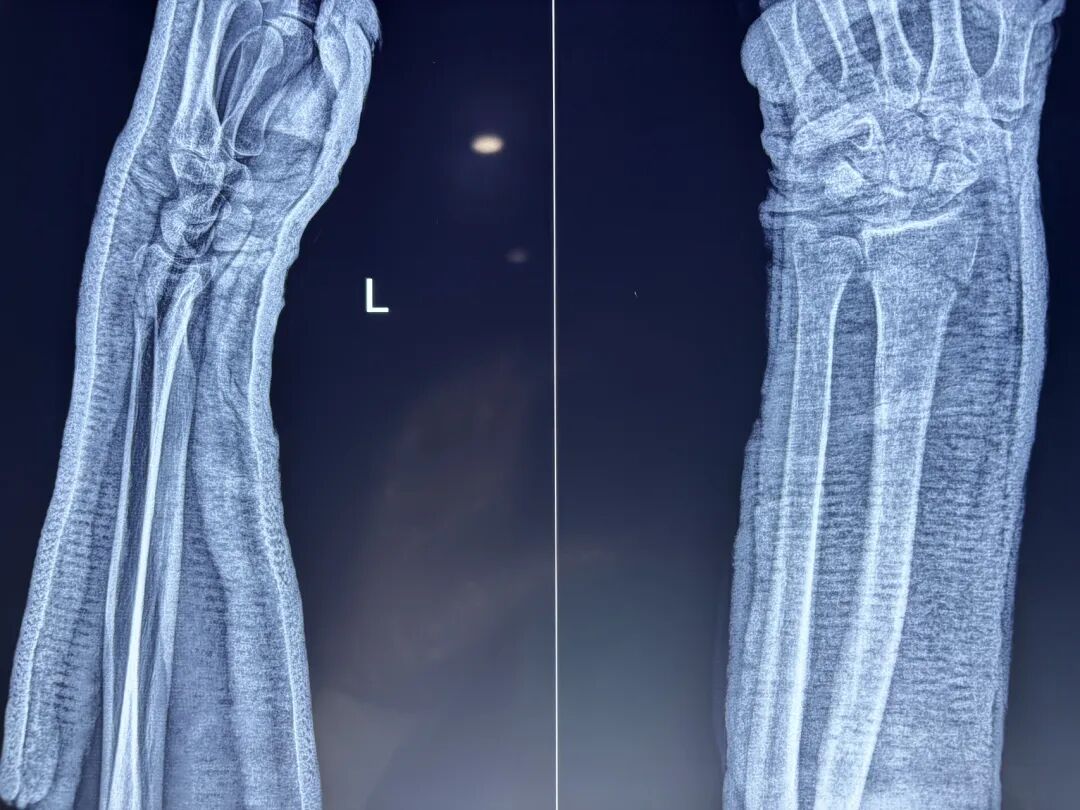

典型克雷氏外观:骨折远端向背侧移位,导致腕关节侧面呈现类似“餐叉”的畸形,即骨折端向背侧突出,形成明显的成角畸形。

这种相互嵌插的克雷氏骨折最容易造成上述复位后残留掌侧角度的问题。

其根本原因在于,牵引复位中直接掌倾只纠正了背侧嵌插。